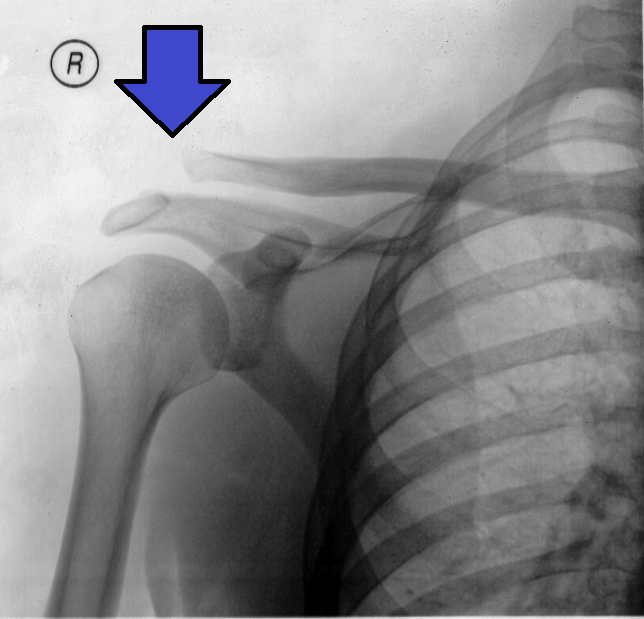

Treatment for Shoulder Separation Treatment of AC separation depends on the severity of the injury. Shoulder injuries Grades I and II usually do not require surgery, while a Grade III injury can require surgical repair if the injury does not heal properly with other treatments. Shoulder separation treatment typically involves: Patient with sling for Shoulder Separation (AC Separation)Managing pain Supporting the shoulder Reestablishing strength and range of motion (physical therapy) Pain management usually includes: Ice or cold packs: Helps with swelling, reducing pain. Sling: Immobilizing the arm for a few days keeps the pain level down. Use of non-steroidal anti-inflammatory drugs (NSAIDs): Medications such as aspirin and ibuprofen.